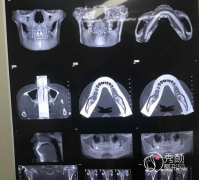

<b>颧骨颧弓手术用什么材料固定比较好,钛钉钛板?钢丝钢板?</b>

颧骨颧弓手术用什么材料固定比较好,钛钉钛板?钢丝钢板?颧骨颧弓手术需要使用钛钉钛板等医用材料进行固定,有些求美